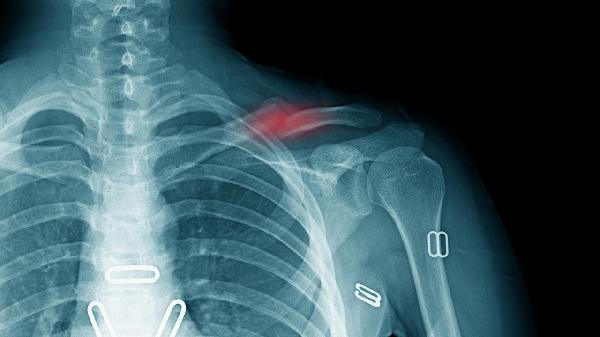

胸椎结核是一种严重的疾病,属于脊柱结核的一种,若不及时治疗可能导致脊柱畸形、神经功能障碍甚至瘫痪。胸椎结核是由结核分枝杆菌感染胸椎引起的,常见症状包括背部疼痛、活动受限、发热、盗汗和体重下降。早期诊断和治疗至关重要,以避免病情恶化。

胸椎结核的发病原因主要与结核分枝杆菌感染有关,感染途径多为血行播散或邻近组织结核病灶的直接蔓延。遗传因素、免疫力低下、营养不良、长期使用免疫抑制剂等都可能增加患病风险。环境因素如居住条件差、卫生状况不佳也会促进结核病的传播。胸椎结核的病理过程包括骨质破坏、椎间盘受累、脓肿形成以及神经压迫,严重时可能导致脊柱后凸畸形和脊髓损伤。